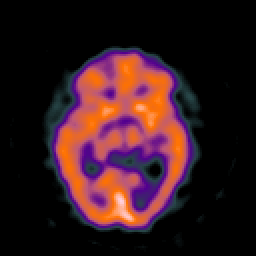

SPECT TC Study #8 -- Slice #25

[Home][Help][Clinical][Tour 1][Tour 2][Tour 3] Slice 25